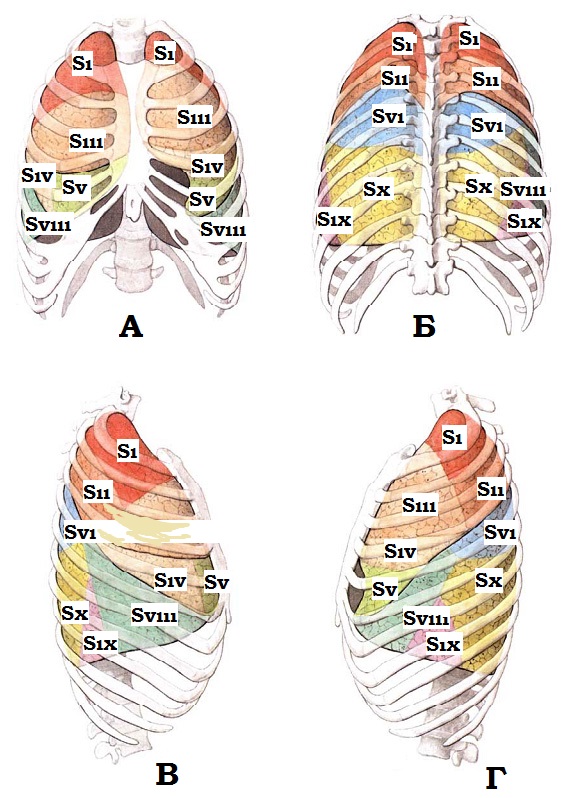

Анатомические изображения сегментов легких различных животных

Раздел: Другие животные